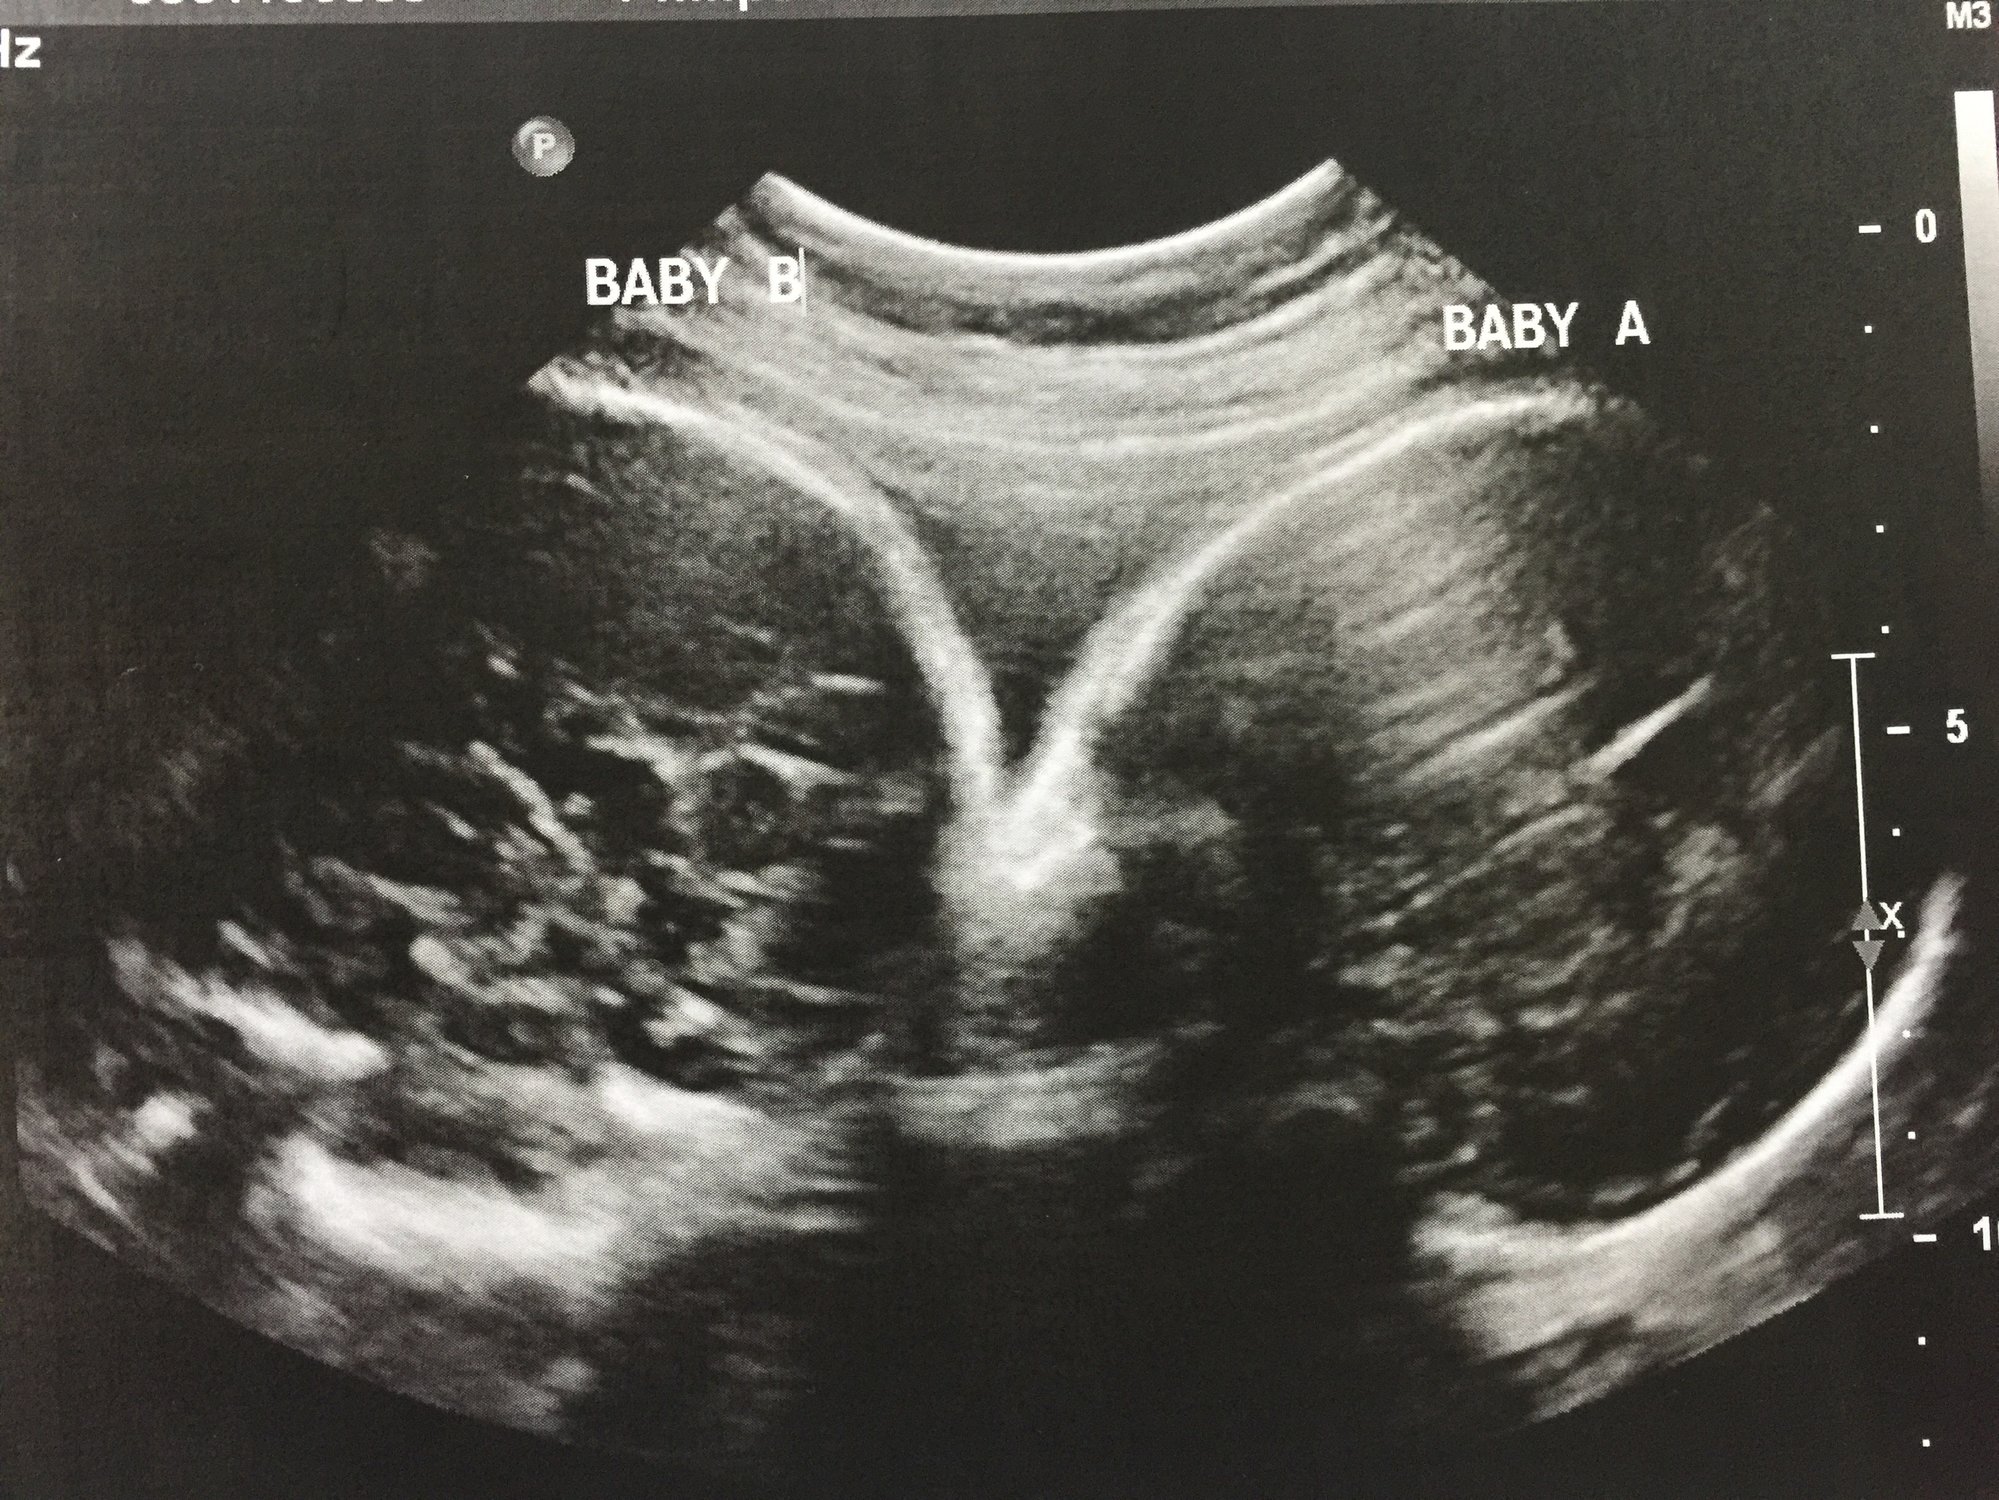

Ladies had my first NST today and it was great babies scored perfect on everything. I also got an ultrasound beforehand and finally got a pick of baby bs profile and a pick of the girls heads. Baby a weighs 3lbs 15 oz and baby b is 4lbs and 6oz crazy the size gap they have always been close in size here are the pics